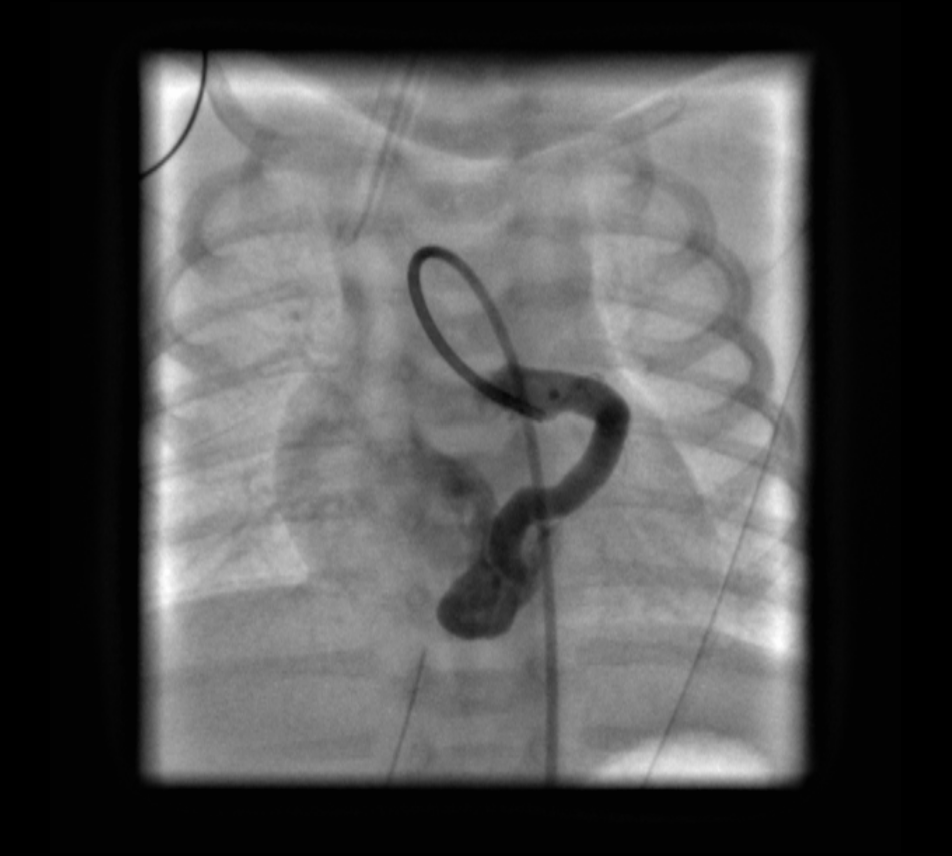

Coronary angiography revealed the fistulous connection to the coronary sinus off of the distal left circumflex coronary artery (LCX). Embolization of the fistula was performed using 2 coils (14 cm × 4 mm distally and 14 cm × 6 mm proximally). Repeated coronary angiography results confirmed the complete occlusion of the fistula and good filling of the left coronary artery (Figures 1-6, fluoroscopic anteroposterior views of the chest).

Figure 1. Angiography catheter positioned within the LMCA showing the dilated course of the LCX.